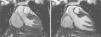

Case reportA 19-year-old woman presented palpitations and chest discomfort, unrelated to exertion and with no pleuritic characteristics, without reports of syncope, during the previous year. She had no relevant medical history and no known relevant family history of cardiac, renal, neurologic or genetic diseases; she was not under any medication and did not practice any sports. Her family physician performed a physical exam that was unremarkable (including blood pressure), except for an arrhythmia on cardiac auscultation. He requested an electrocardiogram (Figure 1A) which revealed sinus arrhythmia, biphasic T waves in leads DII, aVF and V3, and T-wave inversion in leads DIII and V4–V6. On the basis of this abnormal ECG clinical observation by a cardiologist was requested, in which the patient underwent more diagnostic exams. The echocardiogram revealed no significant abnormalities, except the presence of hypertrophic PMs (Figure 1B); LV mass was normal and maximum ventricular wall thickness was 11 mm at the interventricular septum in parasternal long-axis view. There were no significant valvular abnormalities. Despite the presence of prominent PMs, no significant intraventricular gradient or LV outflow tract obstruction was found on Doppler evaluation at rest. For further clarification and to assist with differential diagnosis, CMR imaging was performed. This exam showed a normal right ventricle and normal valve structures. The left ventricle had normal systolic function (60% ejection fraction), with a mass of 59 grams (35.5 g/m2), end-systolic volume of 42 ml and end-diastolic volume of 104 ml. Maximum ventricular wall thickness was 11.2 mm at the interventricular septum measured in end-diastole, 4-chamber view. Both PMs were also seen to be abnormally hypertrophic (Figures 2 and 3), occupying a large part of the LV cavity during systole (Figures 2A and 3A). The anterolateral PM had a maximum diameter of 12.5 mm and the posteromedial PM measured 15 mm on the horizontal axis (end-diastole, short-axis view; Figure 3B). Delayed hyperenhancement was not observed.

(A) 12-lead electrocardiogram showing the repolarization abnormalities described in the text. The voltage sum of the S wave in V1 and the R wave in V5 is 36 mm, but this patient was 19 years old, so the voltage criterion for left ventricular hypertrophy of ≥35 mm is not applicable; (B) echocardiographic image at the level of the papillary muscles (short-axis view at end-systole).